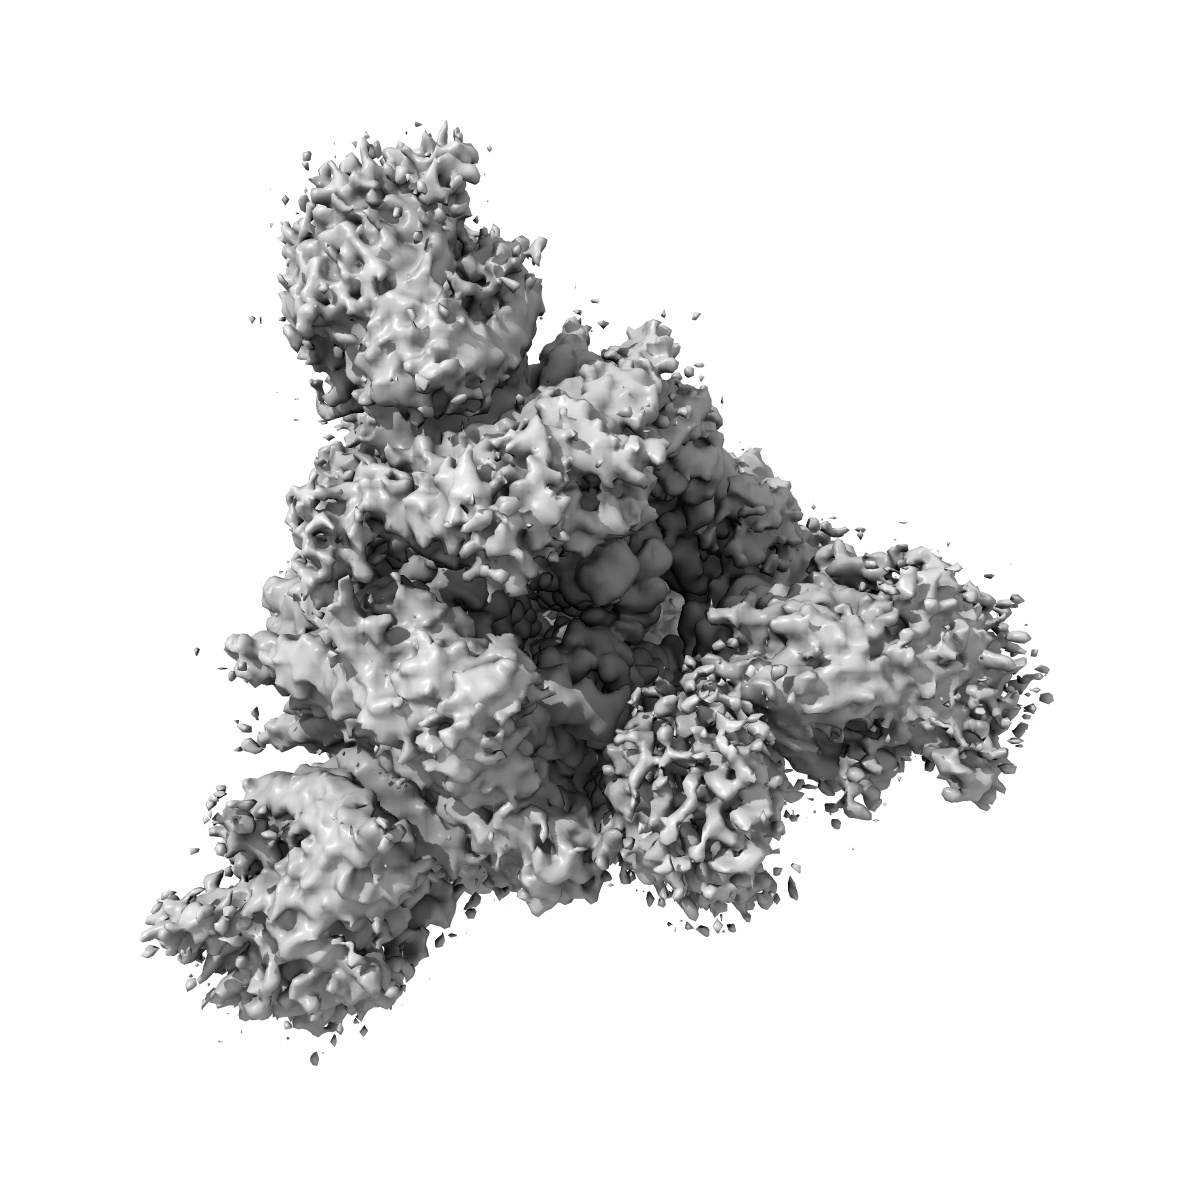

Cryo-EM structure of the SARS-CoV-2 D614G,L452R mutant spike protein ectodomain

Sample: SARS-CoV-2 D614G,L452R mutant spike protein ectodomain

Structural analysis of receptor binding domain mutations in SARS-CoV-2 variants of concern that modulate ACE2 and antibody binding.

Mannar D, Saville JW , Zhu X , Srivastava SS , Berezuk AM, Zhou S, Tuttle KS, Kim A, Li W, Dimitrov DS, Subramaniam S

(2021) Cell Rep , 37 , 110156 - 110156